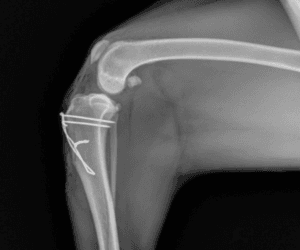

Medial Patellar Luxation

Medial patellar luxation is a condition where the patella (knee-cap) does not stay in its normal position in the groove on the end of the femur (thigh bone) and will pop-out, or luxate, to the medial (inside) surface of the knee. This is a common condition in smaller breed dogs but can occur in any breed. Surgical correction often involves deepening of the trochlear groove, realignment of the patellar tendon and soft tissue reconstruction.

$2250